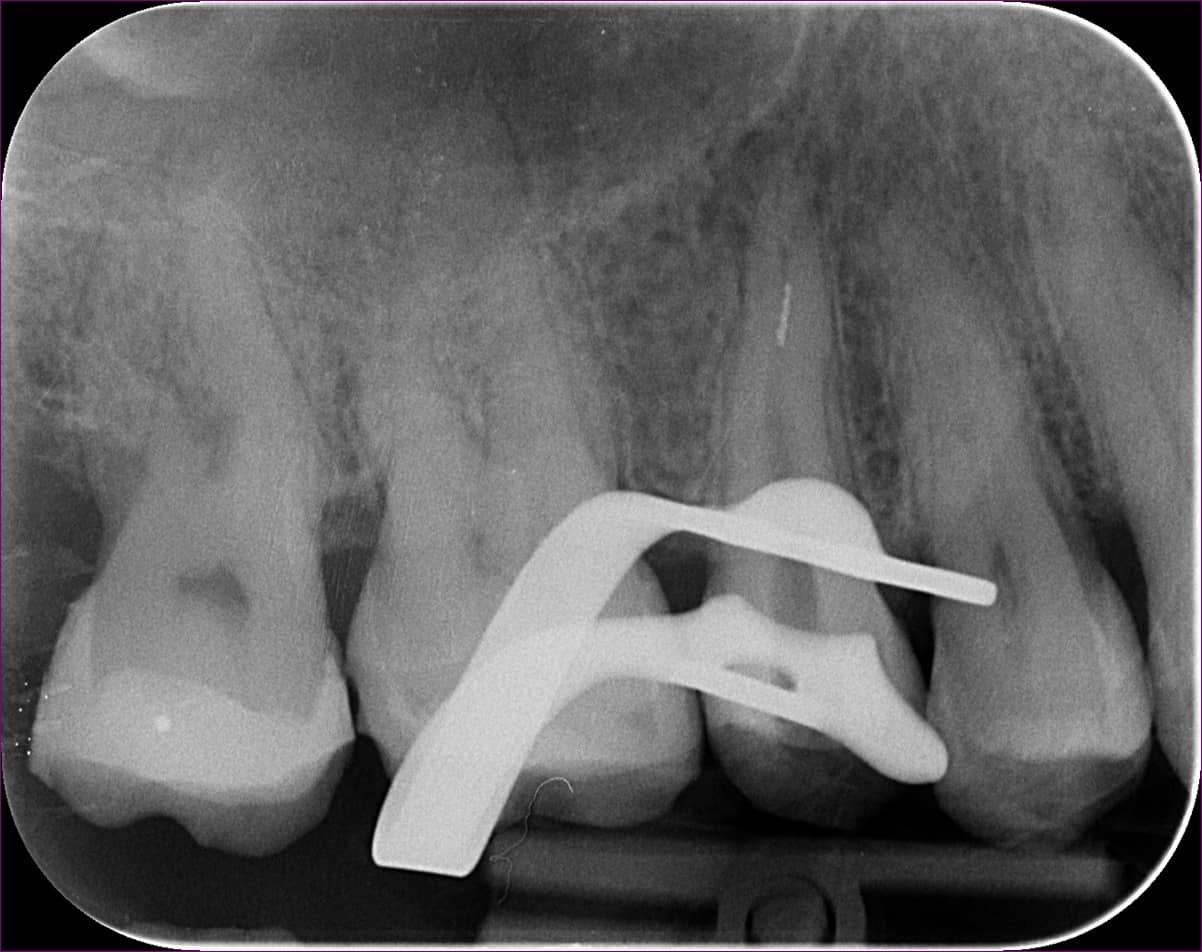

A hölgy örömmel hallotta, hogy hála a mikroszkópos endodonciának, jó eséllyel orvosolható a problémája: így a bajba került fogat meg lehet menteni a kihúzástól. Az érintett jobb felső ötös fogról a páciens már egy kis fogfelvétellel érkezett (lásd fentebb).

A gyökérkezelés menetében az első lépés a diagnózis, amely többek között az érintett fog(ak)ról készített röntgenfelvételen alapul. A röntgen megtekintésekor szakértőnknek feltűnt, hogy valószínűleg nem egy, hanem két betört fragmentumról van szó. Ezek a fogak gyakran két csatornával rendelkeznek, illetve ebben az esetben egy érdekes variációval: a két csatornának közös vége van. Ilyenkor az egymás felé ívelő gyökércsatornák meglehetősen görbék lehetnek – tipikus helyei a tűtöréseknek.

A röntgenfelvétel igazolta a gyanút